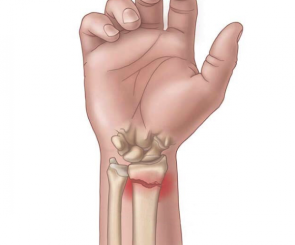

Fratura comum após quedas, afeta o osso do antebraço próximo ao punho. O tratamento pode ser conservador ou cirúrgico.